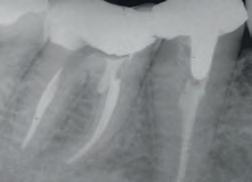

ENDODONTICS • 117–132

Mineral Trioxide Aggregate Repair

Cement

Canal Sealer

Resin-Coated Gutta Percha

File Lubricants

Calcium Hydroxide Paste

Citric Acid

Endodontic Tips Posts and Drills

Light-cured temporary resin